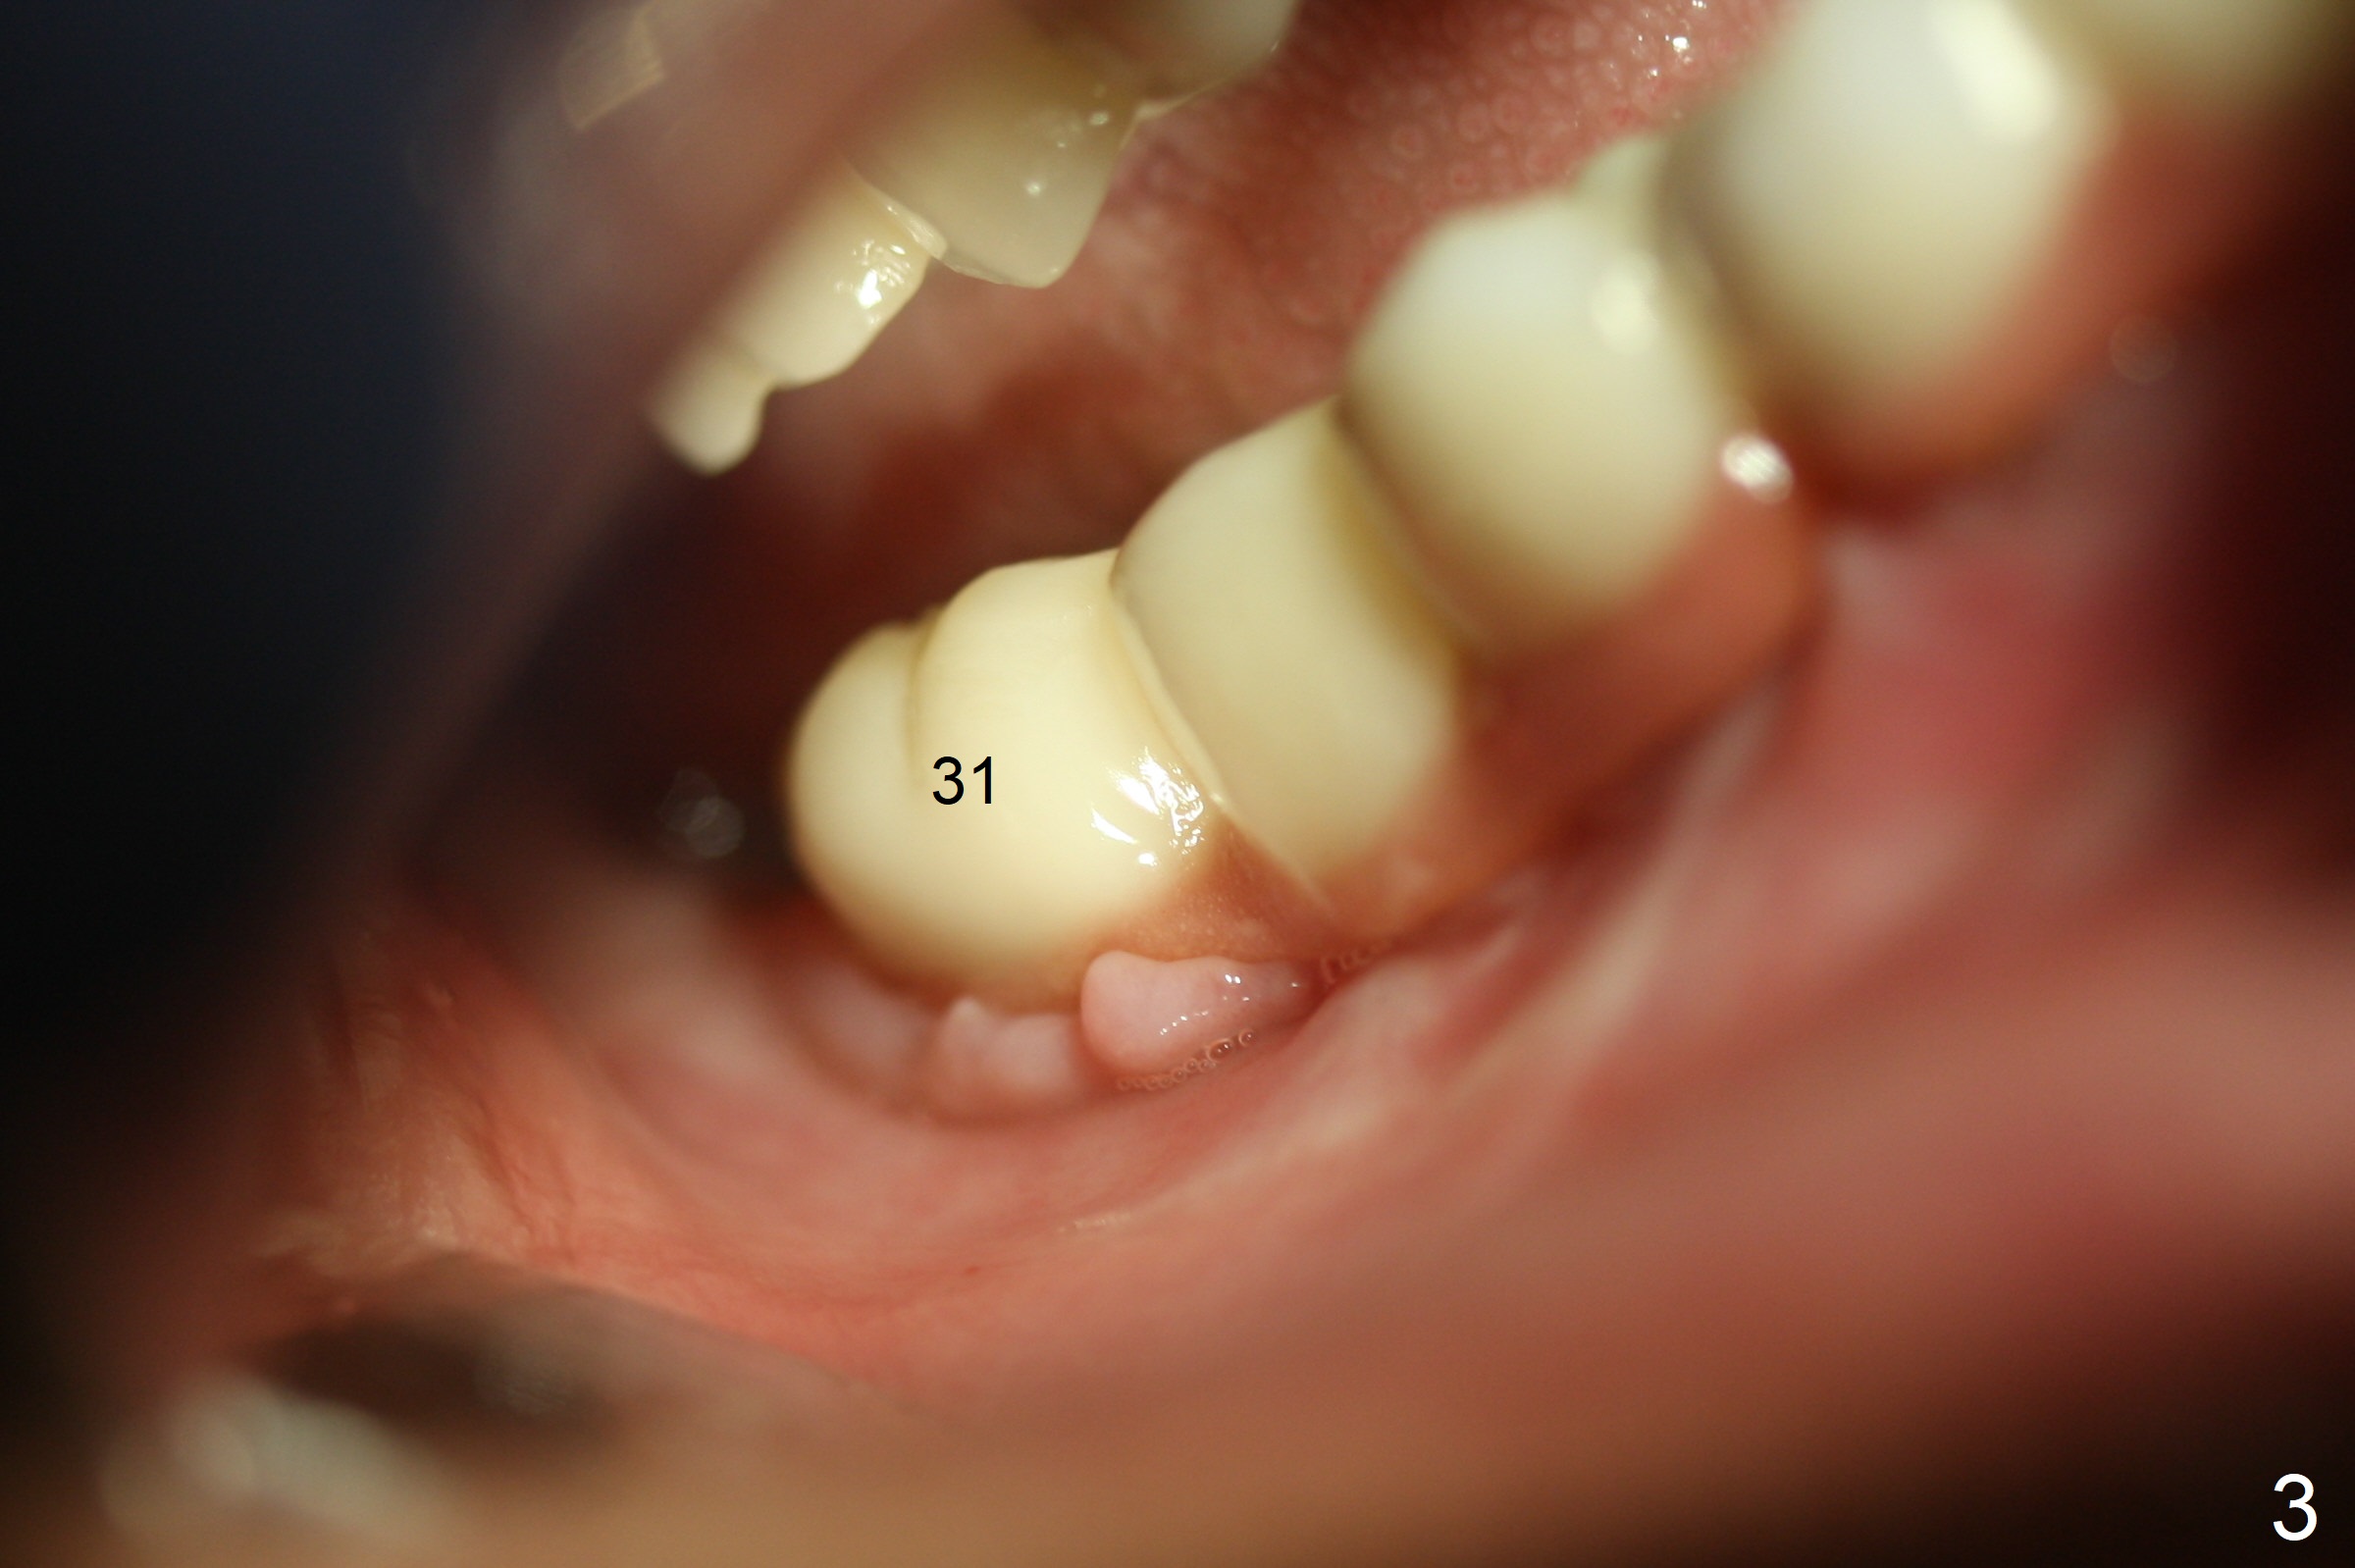

A 56-year-old woman with atrophic jaws requests redoing lower implant restoration (in function 1 year) for cosmetic reason and placing an implant at #19 (because she could not masticate on the left). Note the discrepancy between CR and CO (Fig.1,2). There is gingival hypertrophy at #31 (Fig.3), while the anterior restoration looks short with gingival recession (Fig.4). The patient is pleased instantly when lower anterior provisional is fabricated (Fig.5-7).